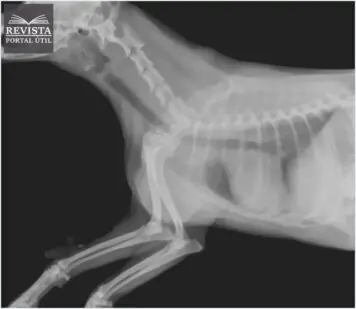

Subdivisões da área de Radiologia: Conheça Todas!

A radiologia é uma área da medicina que possui muitas tecnologias, cada um com seu objetivo e benefícios, são as subdivisões da radiologia. Essa tecnologia pode ser utilizada de diversas […]